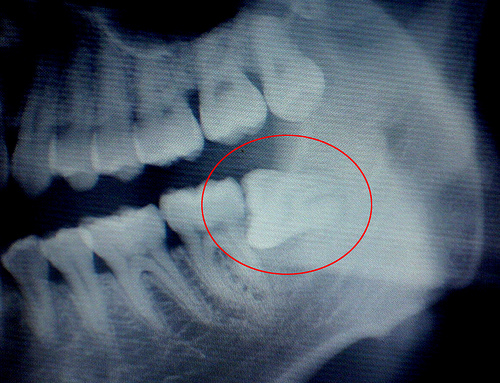

很多人认为只要智齿不疼,就可以不用拔牙,其实这样的观念并不正确,会忽视掉已经形成的一些炎症与龋坏现象,所以建议去正规医院看看智齿的状况,医生会通过口腔检查和x光片进行评估,该智齿需不需要拔。从预防的角度讲,智齿越早拔出越好。

如果智齿不能完全生长出来,其牙冠就会被牙龈覆盖住一部分,从而形成冠周袋。冠周袋很容易积存食物残渣和细菌,可导致智齿冠周炎反复发作,患者会出现牙痛、张口受限、进食困难等症状。其次,如果智齿长歪了,它和相邻的牙齿之间就会出现一个夹角,容易导致食物嵌塞,时间久了,智齿和相邻的牙齿都容易出现蛀牙甚至是牙髓炎。第三,如果智齿生长的位置和方向出现异常,还会影响上下牙齿之间的咬合关系,可能造成颞下颌关节弹响、张口疼痛、夜磨牙等。

6、阻生齿:这种类型的智齿,埋在齿槽骨的里面,当你感觉到痛时,就要拔掉它。